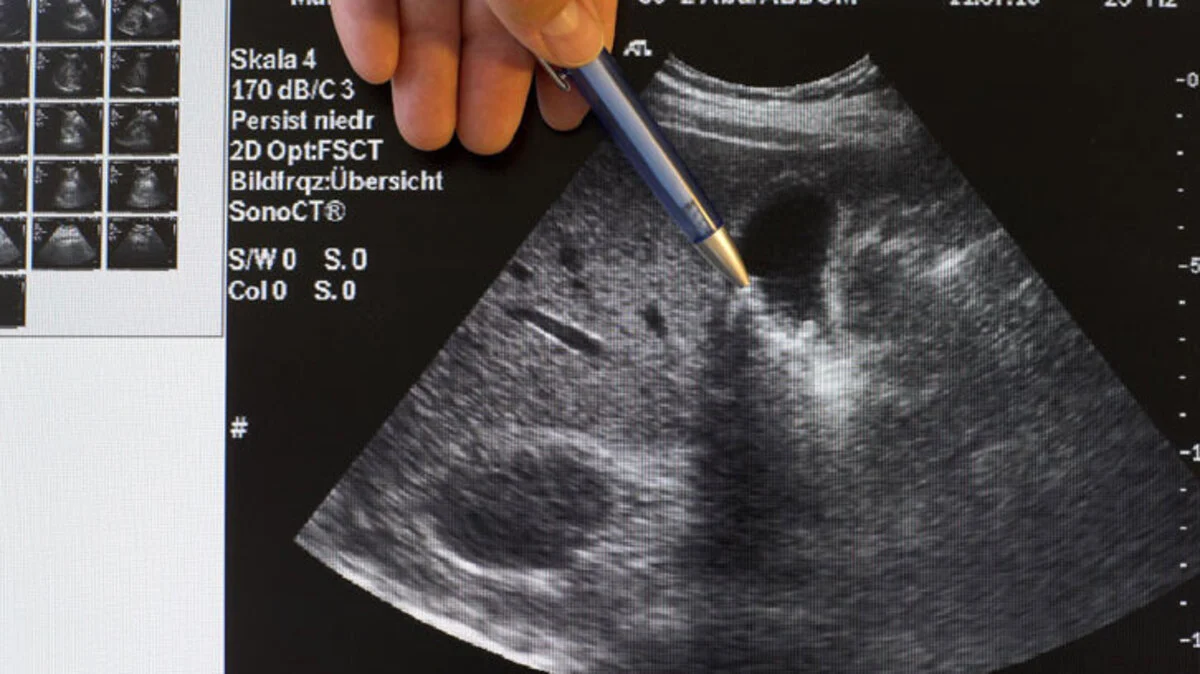

Gallensteine: Fett und Alkohol mit Maß

Heftige, krampfartige, unerträgliche Schmerzen im Oberbauch: Wenn die Galle nach dem üblichen Faschingsmenü mit viel fettem Essen und reichlich Alkohol unter Koliken k. o. geht, ist Gefahr im Verzug.